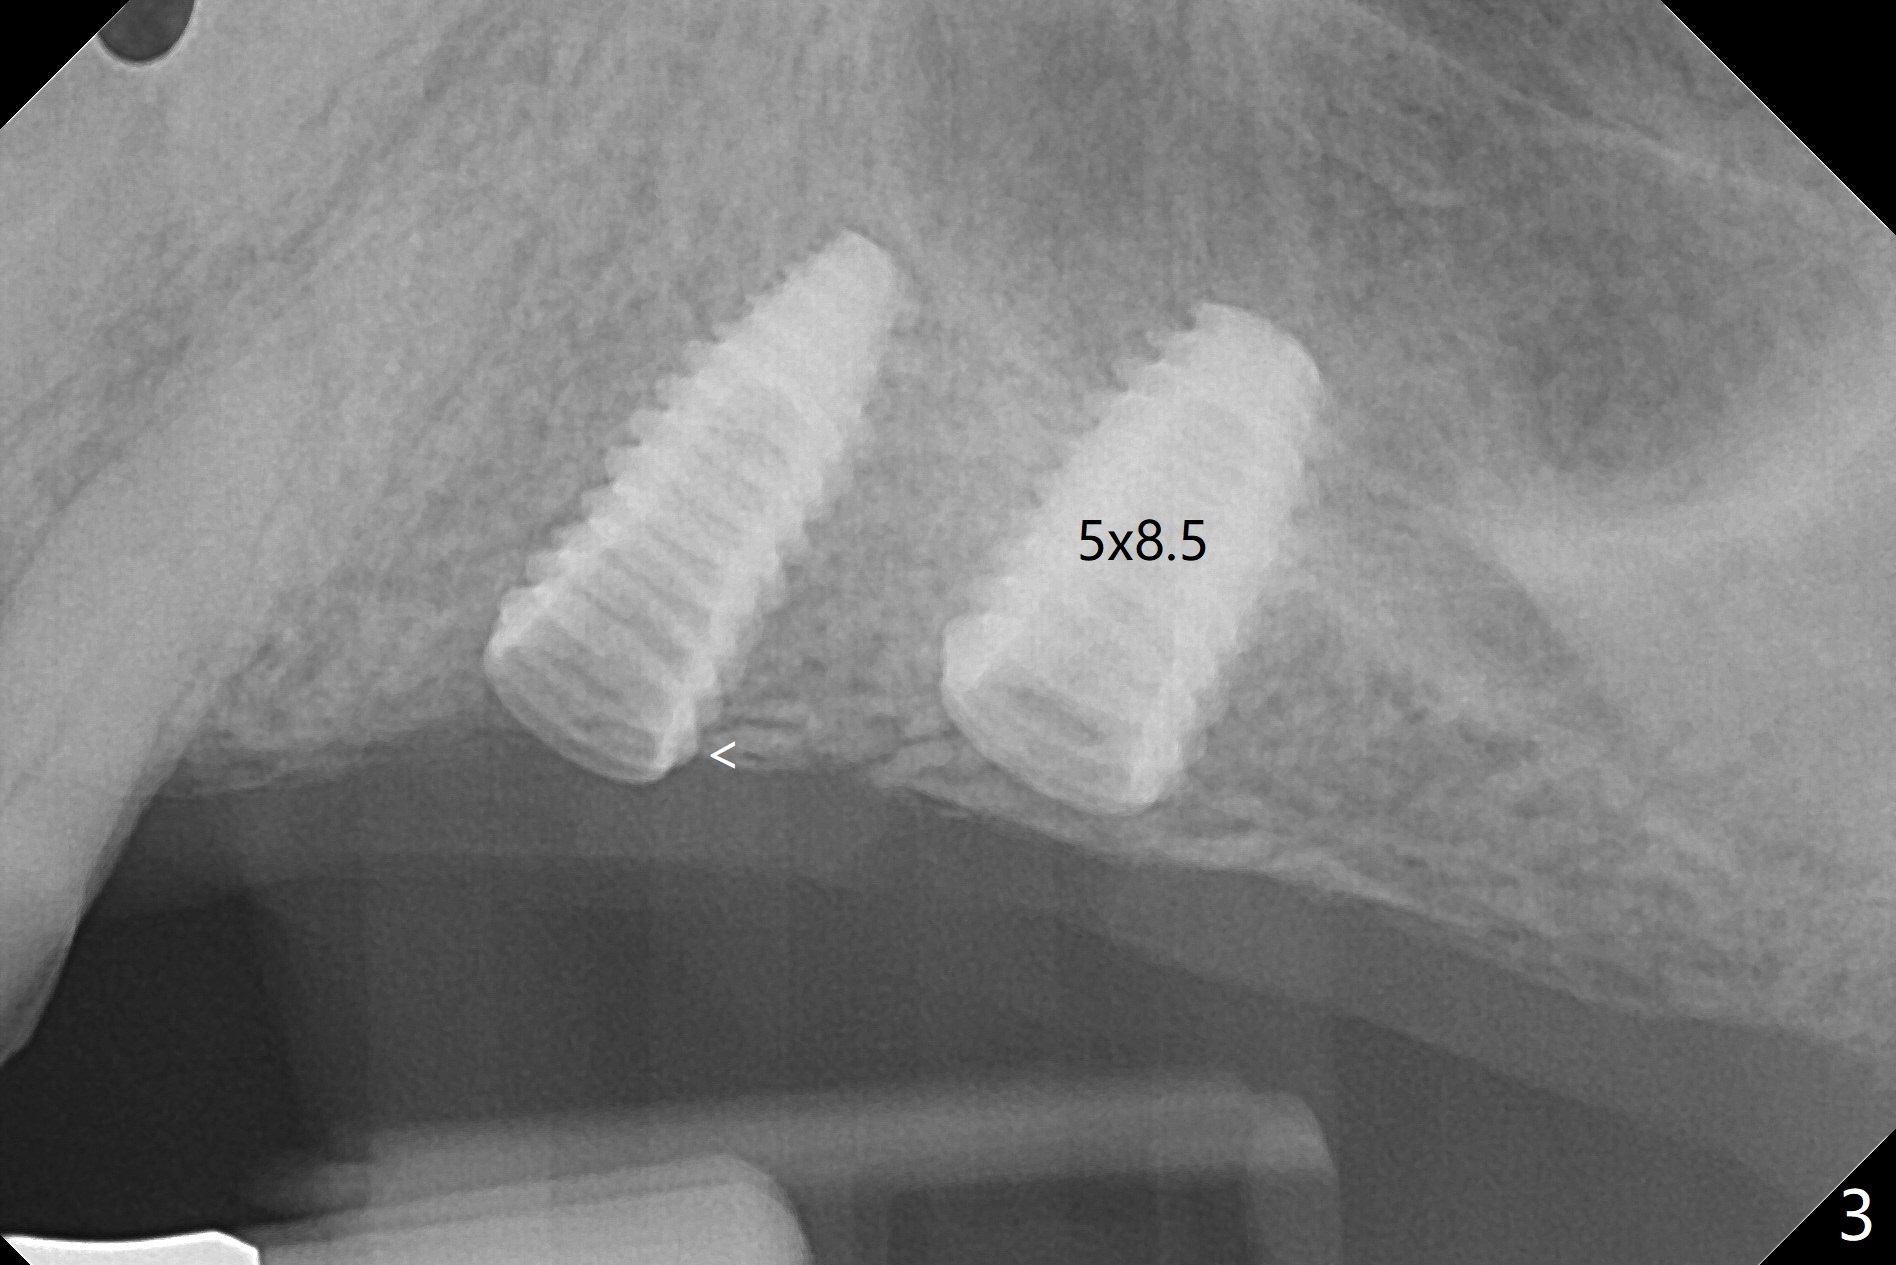

PA is taken after 2.2 mm drill reaches the depth at #13 to confirm that the osteotomy is parallel to the long axis of the tooth #12 (Fig.1). Fixture mount is used to place a 4x10 mm implant at #13 and stays as an anchor pin while osteotomy and sinus lift are being conducted at #14 (Fig.2). In fact there is discrepancy in depth using the guide. For example the last drill for osteotomy is 4.5x7.3 mm according to design, whereas 4.5x11.5 mm drill has to be used before the sinus floor has small area of perforation without sinus membrane breakage. Autogenous bone harvested from the osteotomy, PRF membrane and a 4.5x10 mm dummy implant are used for sinus lift (Fig.2). The placement depth of the implant at #13 has to be adjusted multiple times until satisfaction (Fig.2-5). The implant at #14 is infected and loosened 1.5 months postop; after its removal, the sinus floor is absent without membrane perforation; the large defect with basically intact buccal and palatal walls is grafted (Fig.6 *). Four to five months later, use the same guide and drill sequence until 3.5x7.3 mm drill. Insert a 4x10 mm dummy implant to the 2nd line of 12 mm offset and take 5x5 cm CT to determine the diameter and depth of a final implant. Use healing screw. The pattern of bone graft changes 3 months postop (Fig.7, as compared to Fig.6). Return to Upper Arch Immediate Implant, Trajectory II 矫正,糖尿病,种植水平 Xin Wei, DDS, PhD, MS 1st edition 08/06/2019, last revision 12/06/2020